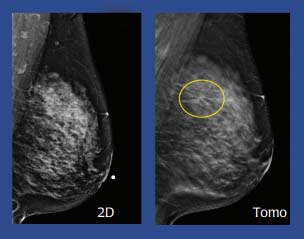

3D Mammography (Tomosynthesis)

3D mammography technology (also known as Tomosynthesis) offers the highest resolution breast scans available. Compared to traditional mammography machines that produce one flat picture, 3D mammography produces layers upon layers of high-resolution images of breast tissue. This allows the radiologist to scroll through your digital mammogram page by page, layer by layer, to look for suspicious masses — allowing for earlier detection should cancer be present. Catching cancer in its earliest stages greatly increases the patient's opportunity for survival. If your 3D image reveals a mass, a BJC physician radiologist that specializes in reading breast imaging can expedite your connection to care. Any necessary treatments, surgeries and support services you need are offered by BJC HealthCare, for your convenience and comfort.